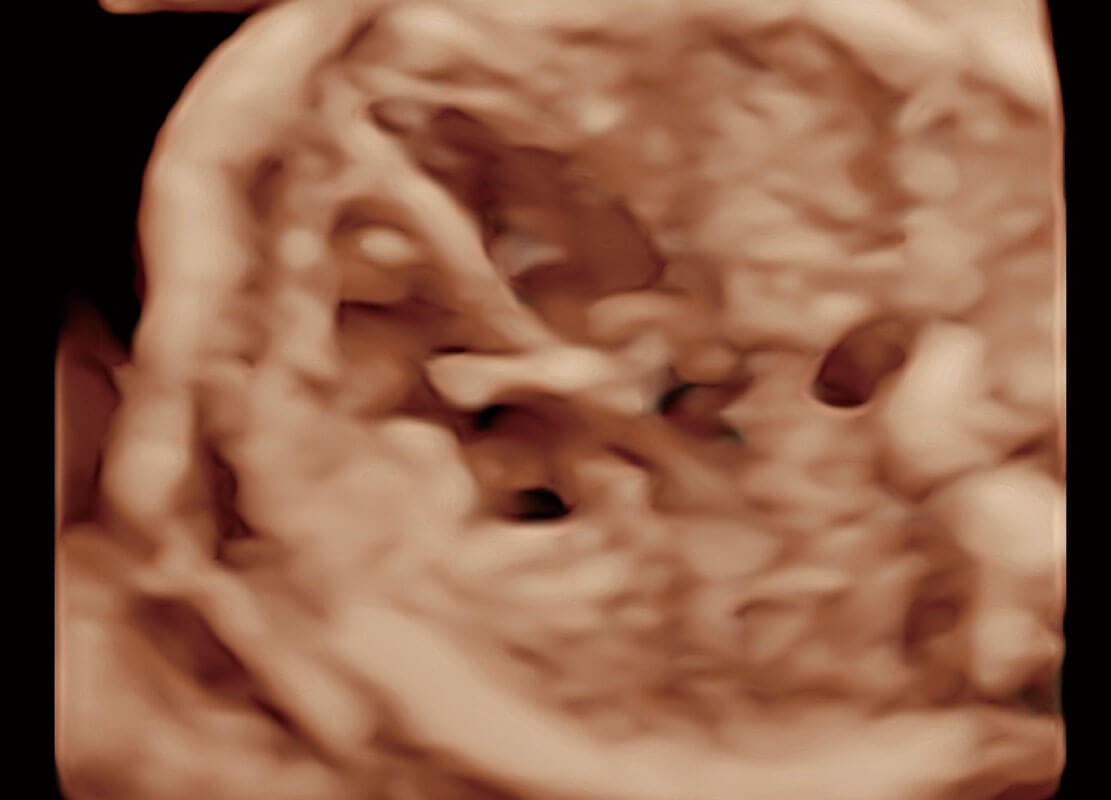

P60在胎儿早孕期超声筛查中为您带来优异的图像质量。

光影成像-孕囊